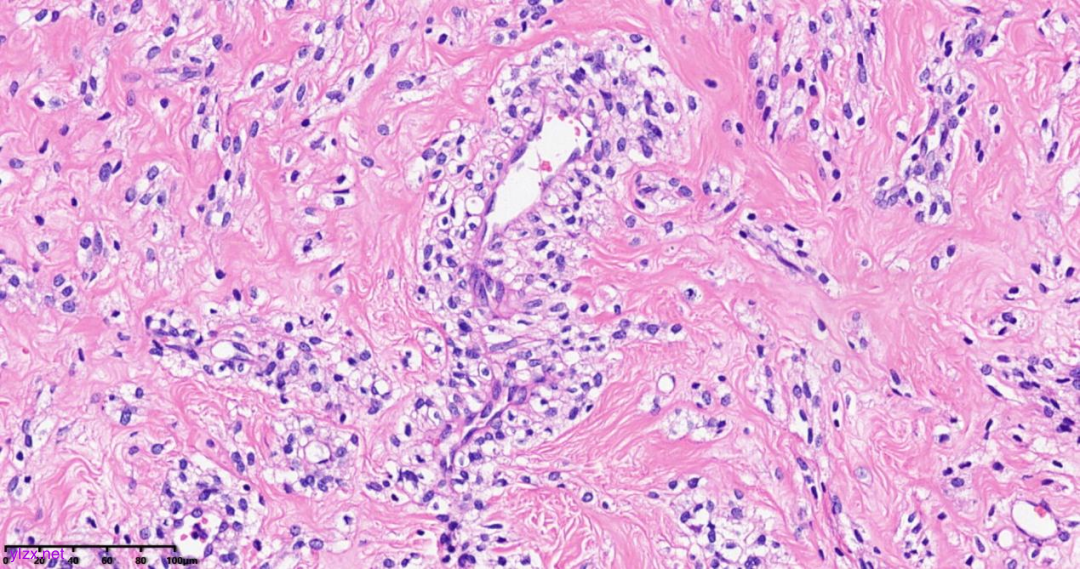

肿瘤细胞以梭形细胞、卵圆形细胞为主,部分为胞浆透亮的上皮样形态,透亮细胞界限较清,胞质淡染或胞浆丰富、嗜酸性,肿瘤内血管丰富,肿瘤细胞围绕血管周围片巢状、束状及放射状排列;肿瘤细胞核异型性不明显,核分裂像少见(<1个/50HPF),染色质开放,可见小核仁;肿瘤间质水肿、黏液变性,纤维胶原增生伴玻璃样变性。

图1~5 低倍镜下:肿瘤细胞以梭形细胞、卵圆形细胞为主,部分为胞浆透亮的上皮样形态,肿瘤细胞分布疏密不均,部分区密集丰富,部分区肿瘤细胞稀少,间质疏松水肿、黏液变性,肿瘤细胞围绕血管周围生长,局部间质纤维胶原增生伴玻璃样变性。

图6 中倍镜下:肿瘤内血管丰富,胞浆透亮的上皮样细胞围绕血管周围片巢状、束状及放射状排列。